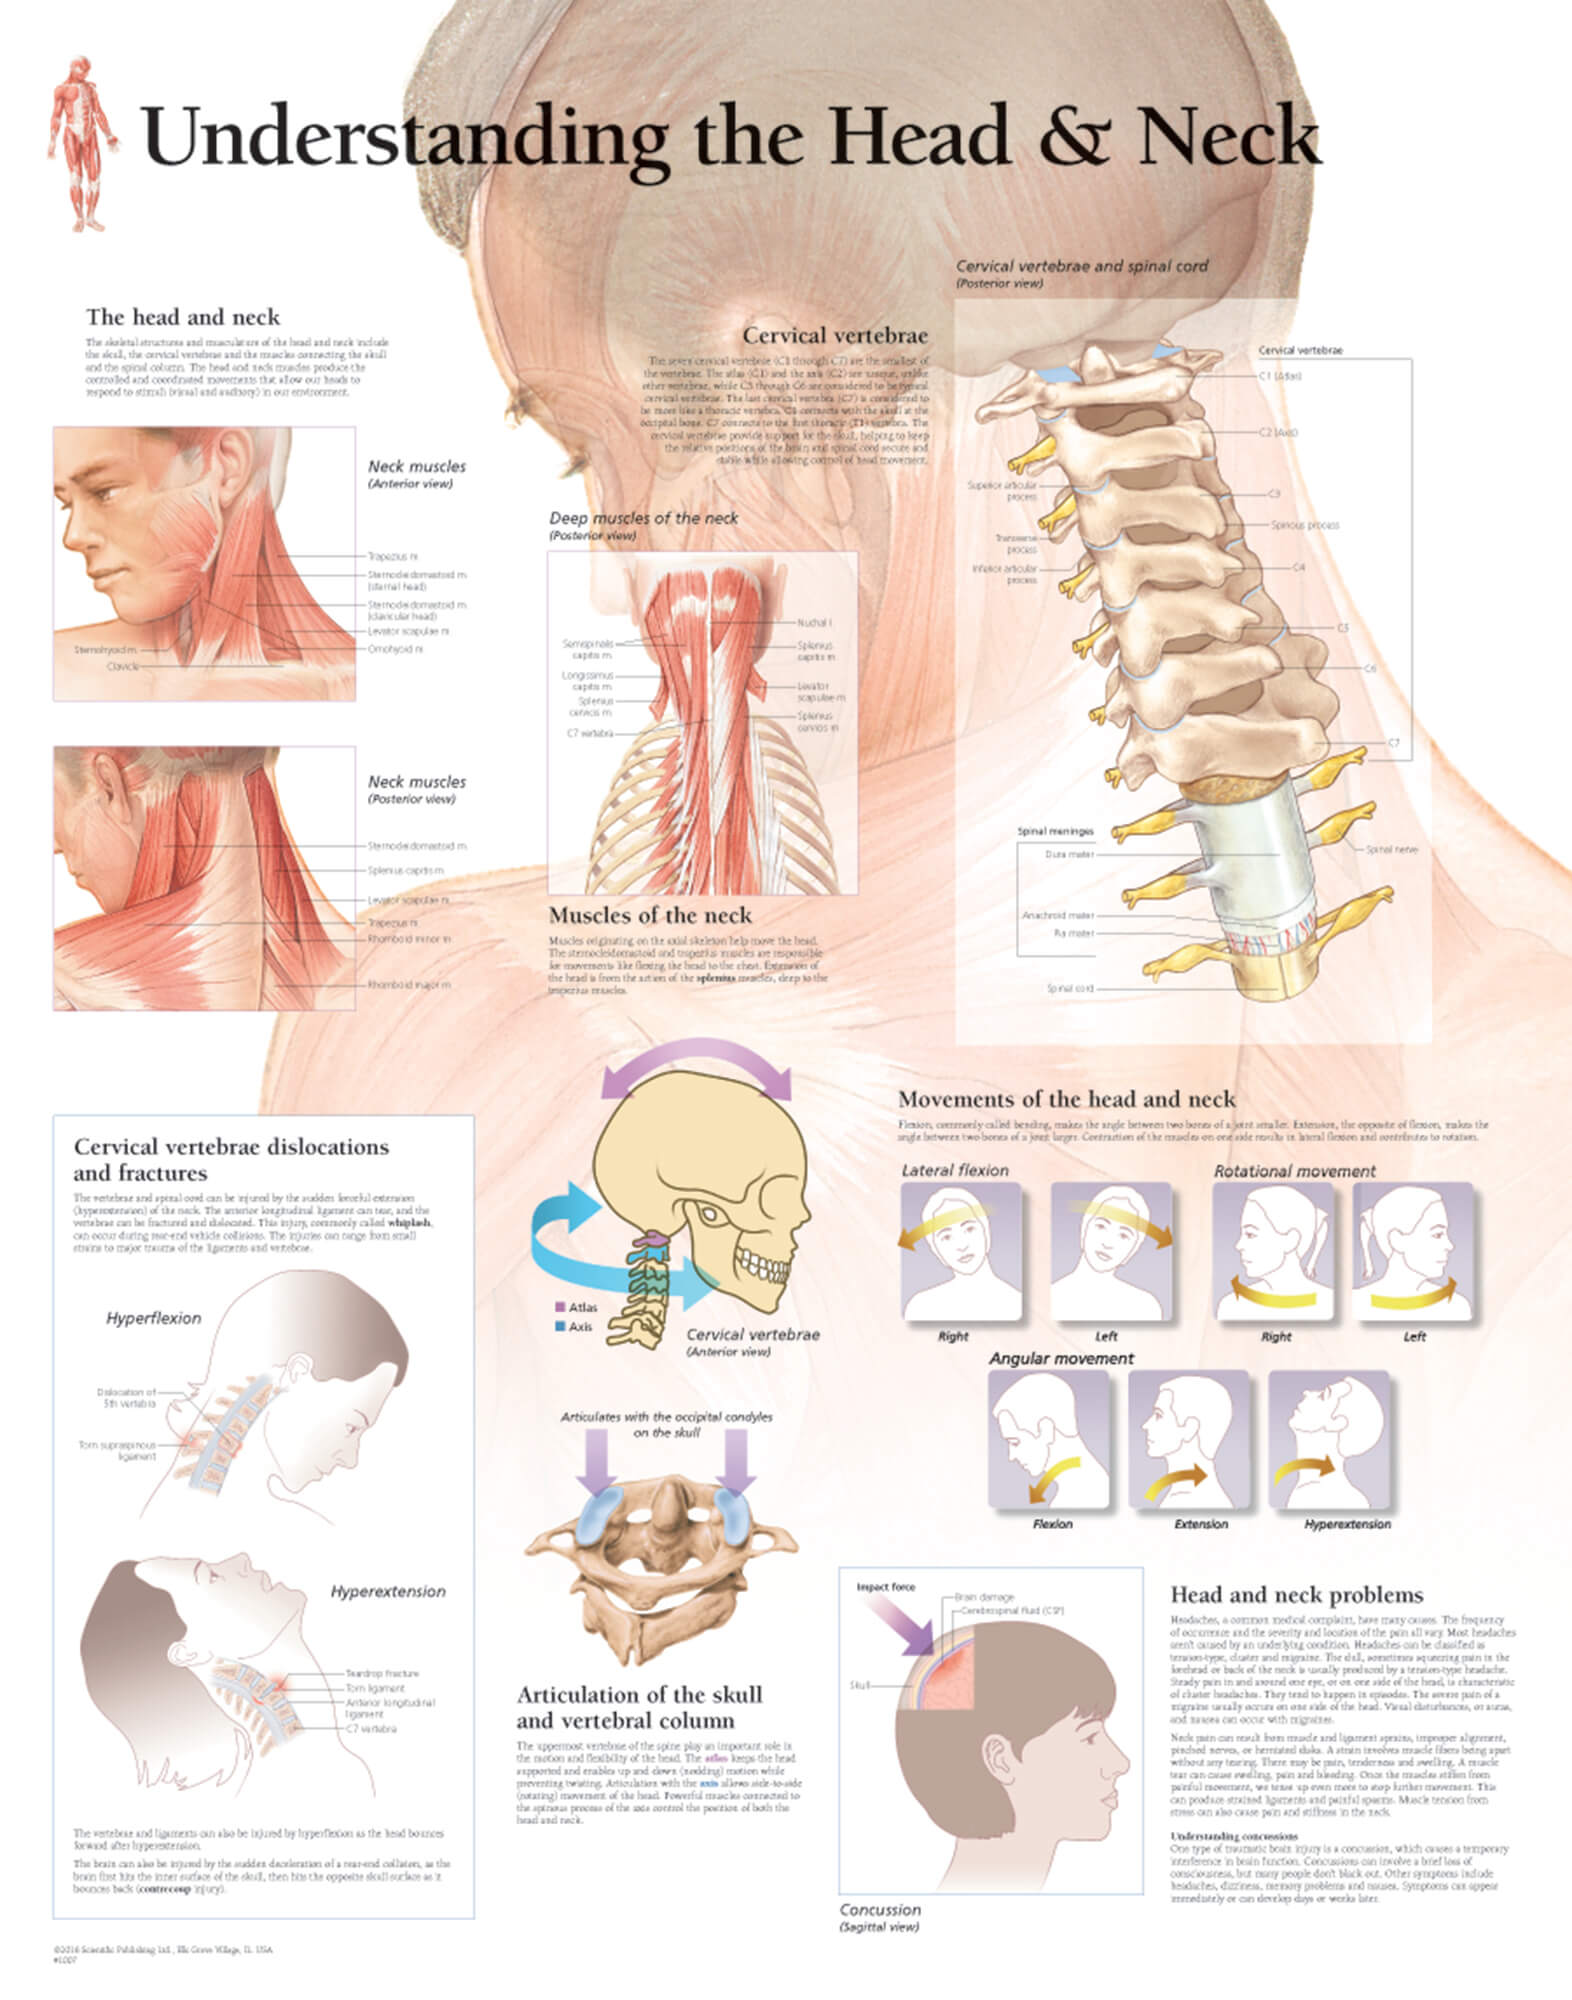

Reference Chart Anatomy and Injuries of the Head and Neck

Understanding the Head & Neck Scientific Publishing